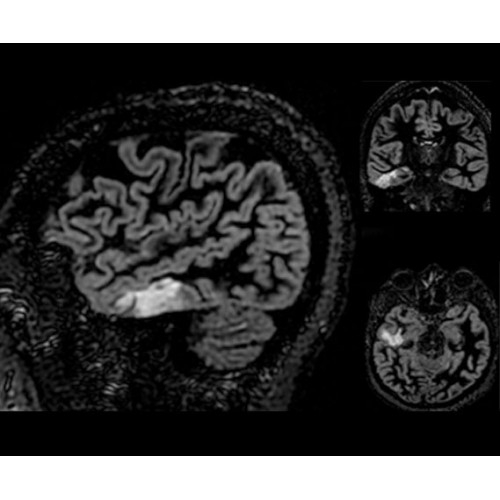

• Специальный пакет приложений для измерения и сравнения объемных изображений ЦНС с нормами поможет вам в диагностике нейродегенеративных заболеваний, а дополнительные инструменты визуализации — в постановке точного диагноза с помощью бета-амилоидов и радиоизотопных маркеров ФДГ.

• In vivo лаборатория — получайте полные данные биохимических процессов in vivo с мультиядерной спектроскопией на SIGNA PET/MR.